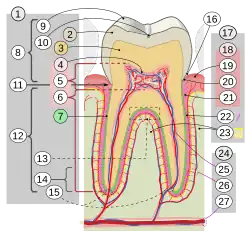

Jeder (echte) Zahn besteht aus der Zahnkrone (Corona dentis), dem Zahnhals (Cervix dentis, seltener: Collum dentis) und der Zahnwurzel (Radix dentis) und ist aus mehreren Schichten aufgebaut. Bei einem gesunden Zahn sieht man nur den Zahnschmelz, der wie eine Glasur das innen liegende Zahnbein (Dentin) bedeckt. Das Dentin wiederum umschließt das Zahnmark (Pulpa). Die Wurzel wird bis zum Zahnhals von Wurzelzement (Cementum) und Wurzelhaut umschlossen.

Zahnschmelz (Enamelum)

Der Zahnschmelz (Latein: Enamelum) ist die härteste Substanz des menschlichen Körpers mit einer Vickershärte von 250 bis 550 und einer Druckfestigkeit von 300 bis 450 MPa. Sein Elastizitätsmodul beträgt 50.000–85.000 MPa (Körber, 1995).[7] Der Zahnschmelz wird von schmelzbildenden Zellen, den Adamantoblasten (auch Ameloblasten genannt), gebildet. Er besteht zu 95 Prozent aus Hydroxylapatit (Ca5(PO4)3 OH), einem kristallinen Material, dessen Hauptanteile Calcium und Phosphat sind. Der Zahnschmelz ist für wasserlösliche Stoffe geringfügig durchlässig, zum Beispiel für seine Bestandteile Calcium und Phosphat, sowie für Fluoride. Mit Hilfe von Fluoriden wird das Hydroxylapatit in das härtere Fluorapatit (Ca5(PO4)3(F)) umgewandelt. Deshalb werden diese zur Härtung des Zahnschmelzes in Zahnpasten verwendet. Hingegen können Säuren dem Zahn schaden, weil sie aus dem Zahnschmelz das Calcium und Phosphat herauslösen und ihn damit aufweichen (siehe Karies).

Zahnbein (Dentin)

Unter dem Zahnschmelz liegt das Zahnbein. Es stellt die Hauptmasse des Zahnes dar. Die Hartsubstanz des Dentins besteht wie beim Zahnschmelz aus Calcium und Phosphat, allerdings nur zu zwei Dritteln, der Rest ist Eiweiß und Wasser, weshalb Dentin weicher und anfälliger gegen Karies ist als der Zahnschmelz. Das Dentin ist schmerzempfindlich. Hitze-, Kälte- und Berührungsreize führen zu Flüssigkeitsbewegungen in den Dentinkanälchen (die im Bereich des Zahnhalses bis an die Oberfläche reichen können). Dies reizt die Tomes'schen Fasern, Zellfortsätze der Odontoblasten (dentinbildende Zellen). Die Odontoblasten stehen mit freien Nervenendigungen in Verbindung, die den Reiz als Schmerzempfindung ans Zentralnervensystem weiterleiten.

Das Dentin ist wesentlich elastischer als der Zahnschmelz (Elastizitätsmodul 15.000–20.000 MPa), da es über einen deutlich höheren Anteil an organischer Substanz verfügt. Die Vickershärte beträgt beim Zahnbein 60–70 und die Druckfestigkeit liegt bei 200–350 MPa (Körber, 1995).[7]

Zahnmark (Pulpa)

Das Dentin umschließt wiederum den inneren Teil des Zahns, die Pulpa (Zahnmark), das von Blutgefäßen und Nervenfasern durchzogen wird und den Zahn ernährt. Die Nervenfasern der Oberkieferzähne entstammen dem Nervus infraorbitalis, die der Unterkieferzähne dem Nervus alveolaris inferior. Der Zahn besitzt kein Lymphabflusssystem – mit ein Grund dafür, dass eine Pulpitis („Zahnnerventzündung“) nicht wieder abheilen kann.

Wurzelzement (Cementum)

Im Wurzelbereich wird das Dentin vom Wurzelzement (neutr.), (Latein: Cementum, seltener: Substantia ossea dentis) bedeckt, der dritten Zahnhartsubstanz neben dem Zahnschmelz und dem Dentin. Das Wurzelzement, das Wurzeldentin als dünne Schicht umschließend, ist im Bereich der Zahnwurzel die äußere Hülle des Zahnes und „mauert“ diese im Kiefer ein. Doch hat die Verbindung zum Kieferknochen, in dem jeder Zahn in seinem Zahnfach (Alveole) aufgehängt ist, eine gewisse Elastizität (siehe Zahnhalteapparat).

Das Wurzelzement ist in seiner Struktur wie auch Härte dem menschlichen Knochen ähnlich (Druckfestigkeit 15 kg/mm², Zugfestigkeit 10 kg/mm²).[8] Er gehört bereits zum Zahnhalteapparat, da an ihm die parodontalen Fasern ansetzen, die die Zähne in der Alveole beweglich verankern (Hellwig u. a., 1999b).[7]

Zahnbefestigung

Als Wurzelhaut (Syn.: Periodontium) wird das Bindegewebe des Zahnhalteapparates bezeichnet. Diese Sharpey-Fasern, zum Periost gehörende Kollagen-Faserbündel, die in der Knochengrundsubstanz befestigt sind, bilden die Verbindung zum Wurzelzement des Zahnes. An ihnen ist der Zahn federnd befestigt und überbrückt den wenige Zehntel Millimeter breiten Spalt (Periodontalspalt) zwischen dem Zahnzement der Zahnwurzel und der knöchernen Wand des Zahnfachs (Alveole), der Lamina dura. Am Zahnhals wird der Periodontalspalt durch den supraalveolären Faserapparat (frühere Bezeichnung: Ligamentum circulare) abgedichtet.